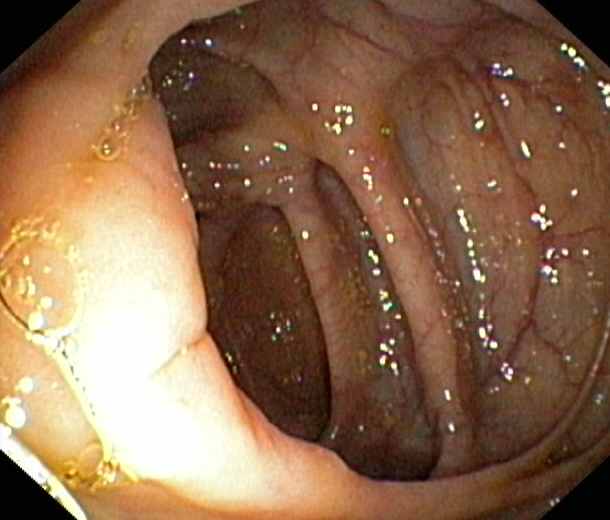

Ileocaecal valve